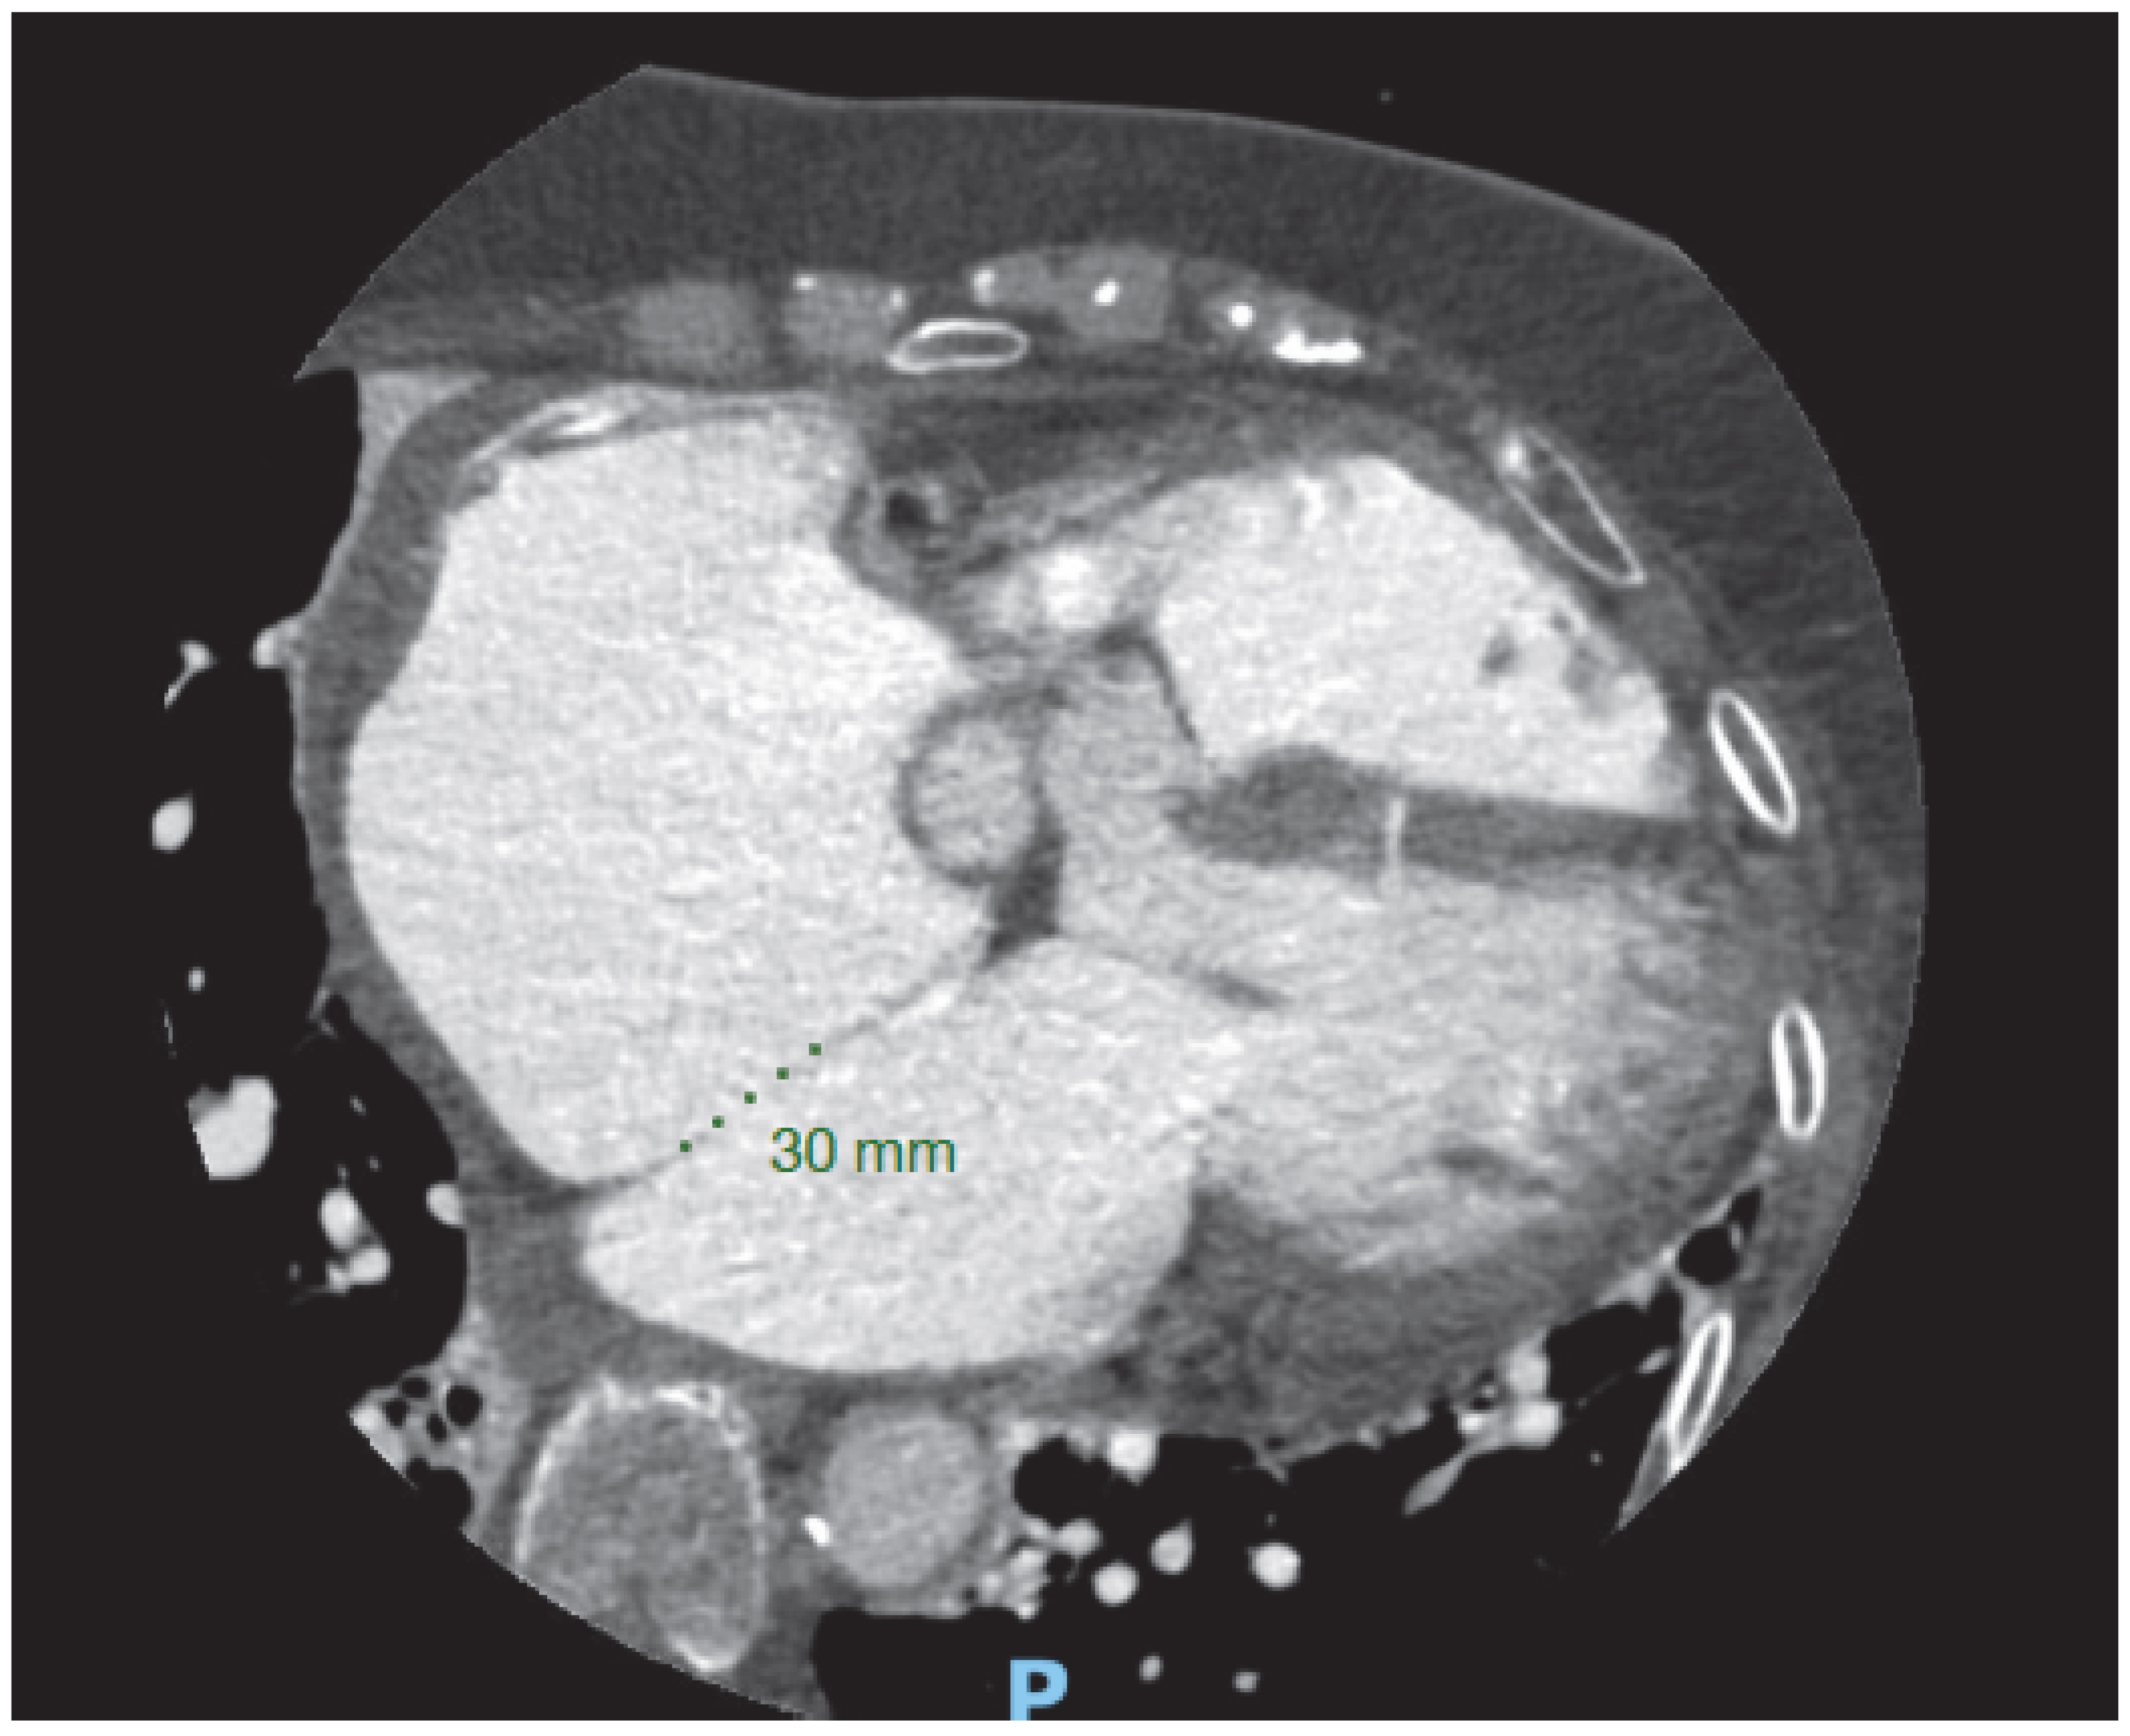

Post-procedure cardiac CT information in assessing prosthetic valve function and structure. Following TAVR, cardiac CT imaging may be appropriate in cases where there is clinical concern for valve thrombosis, endocarditis, or structural deterioration of the prosthetic valve. Valve thrombosis is typically suspected when echocardiography shows increased transvalvular gradients, especially if accompanied by symptoms of aortic stenosis [47]. Signs of leaflet thrombosis include hypoattenuated thickening of the valve leaflets (HALT) and limited leaflet motion, referred to as hypoattenuation affecting motion (HAM). This thickening often has a crescent-like shape, and is more pronounced at the base of the leaflet (Figure 7). These findings should be documented in terms of location, extent, and thickness, and whether leaflet motion is restricted should also be noted. Differentiation between true HALT and beam hardening is important; true hypoattenuation is characterized by consistent localization within the leaflet tissue and correlates with restricted leaflet motion, whereas beam hardening artifacts typically appear as irregular streaks adjacent to the metallic stent and do not correspond to leaflet dysfunction.

Valve thrombosis classification is based on the percentage of sinus of Valsalva thrombosis occupation seen in the MSCT as HALT, using grades 1 to 4, defined as >25%, 26–50%, 51–75% and >75%, respectively.

Most HALT cases with restricted motion are asymptomatic. Oral anticoagulation has been linked to a lower risk of developing HALT or HAM and can help reverse thickening when it occurs. However, the benefit of treating subclinical leaflet thrombosis remains uncertain, and it is unclear whether this approach reduces the risk of future valve degeneration. In a large real-world population undergoing TAVR and routine CTA screening 30 days afterward, HALT was detected in 12% of cases and was independently linked to increased long-term mortality [51].